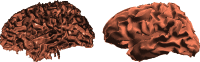

Subject-specific four-layer boundary element method (BEM) electrical forward head models for four participants, generated from magnetic resonance (MR) head images using NFT ( www.sccn.ucsd.edu/wiki/NFT ), were used to simulate electroencephalographic (EEG) scalp potentials at 256 recorded electrode positions produced by single current dipoles of a 3-D grid in brain space. Locations of these dipoles were then estimated using gradient descent within five template head models fit to the electrode positions. These were: a spherical model, three-layer and four-layer BEM head models based on the Montreal Neurological Institute (MNI) template head image, and these BEM models warped to the recorded electrode positions. Smallest localization errors (4.1-6.2 mm, medians) were obtained using the electrode-position warped four-layer BEM models, with largest localization errors (~20 mm) for most basal brain locations. When we increased the brain-to-skull conductivity ratio assumed in the template model scalp projections from the simulated value (25:1) to a higher value (80:1) used in earlier studies, the estimated dipole locations moved outwards (12.4 mm, median). We also investigated the effects of errors in co-registering the electrode positions, of reducing electrode counts, and of adding a fifth, isotropic white matter layer to one individual head model. Results show that when individual subject MR head images are not available to construct subject-specific head models, accurate EEG source localization should employ a four- or five-layer BEM template head model incorporating an accurate skull conductivity estimate and warped to 64 or more accurately 3-D measured and co-registered electrode positions.